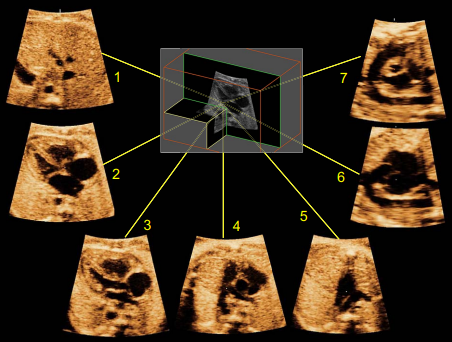

سونوگرافی 4 بعدی (چهار بعدی). سونوگرافی 4 بعدی از پروب مخصوصی استفاده می کند که قادر به گرفتن یک سری تصاویر از قلب جنین در حال تپش است. این تصاویر را می توان در چندین هواپیما به طور همزمان روی صفحه نمایش مشاهده کرد. همچنین می توان آنها را بازسازی کرد تا تصویر واقعی تری از قلب جنین ارائه کند. این به دکتری که معاینه را انجام می‌دهد کمک می‌کند بیماری‌هایی را که می‌تواند بر قلب نوزاد تأثیر بگذارد، بهتر درک کند و تشخیص دهد.

ناهنجاری های مشکوک را می توان با استفاده از چندین روش تصویربرداری ارزیابی کرد، اگرچه معاینه را می توان برای ناهنجاری های خاص قلبی جداگانه ارزیابی کرد . سونوگرافی در مقیاس خاکستری بلادرنگ و تکنیک های سونوگرافی داپلر مکمل (به عنوان مثال طیفی و رنگی) اغلب استفاده می شود. اکوکاردیوگرافیM-mode و سونوگرافی داپلر نیز ابزارهای مهمی برای تجزیه و تحلیل دیس ریتمی قلب جنین هستند. نتایج اضافی، از سونوگرافی سه بعدی (3 بعدی) و 4 بعدی، ممکن است اطمینان تشخیصی را برای توصیف دقیق برخی از ضایعات پیچیده افزایش دهد.

یک تصویر دو بعدی (مطالعه 2 بعدی و 3 بعدی) از قلب جنین می سازد که همانطور که در ویدیوی بالا سمت چپ مشاهده می شود، روی صفحه نمایش داده می شود و قلب طبیعی جنین را با 4 حفره نشان می دهد.